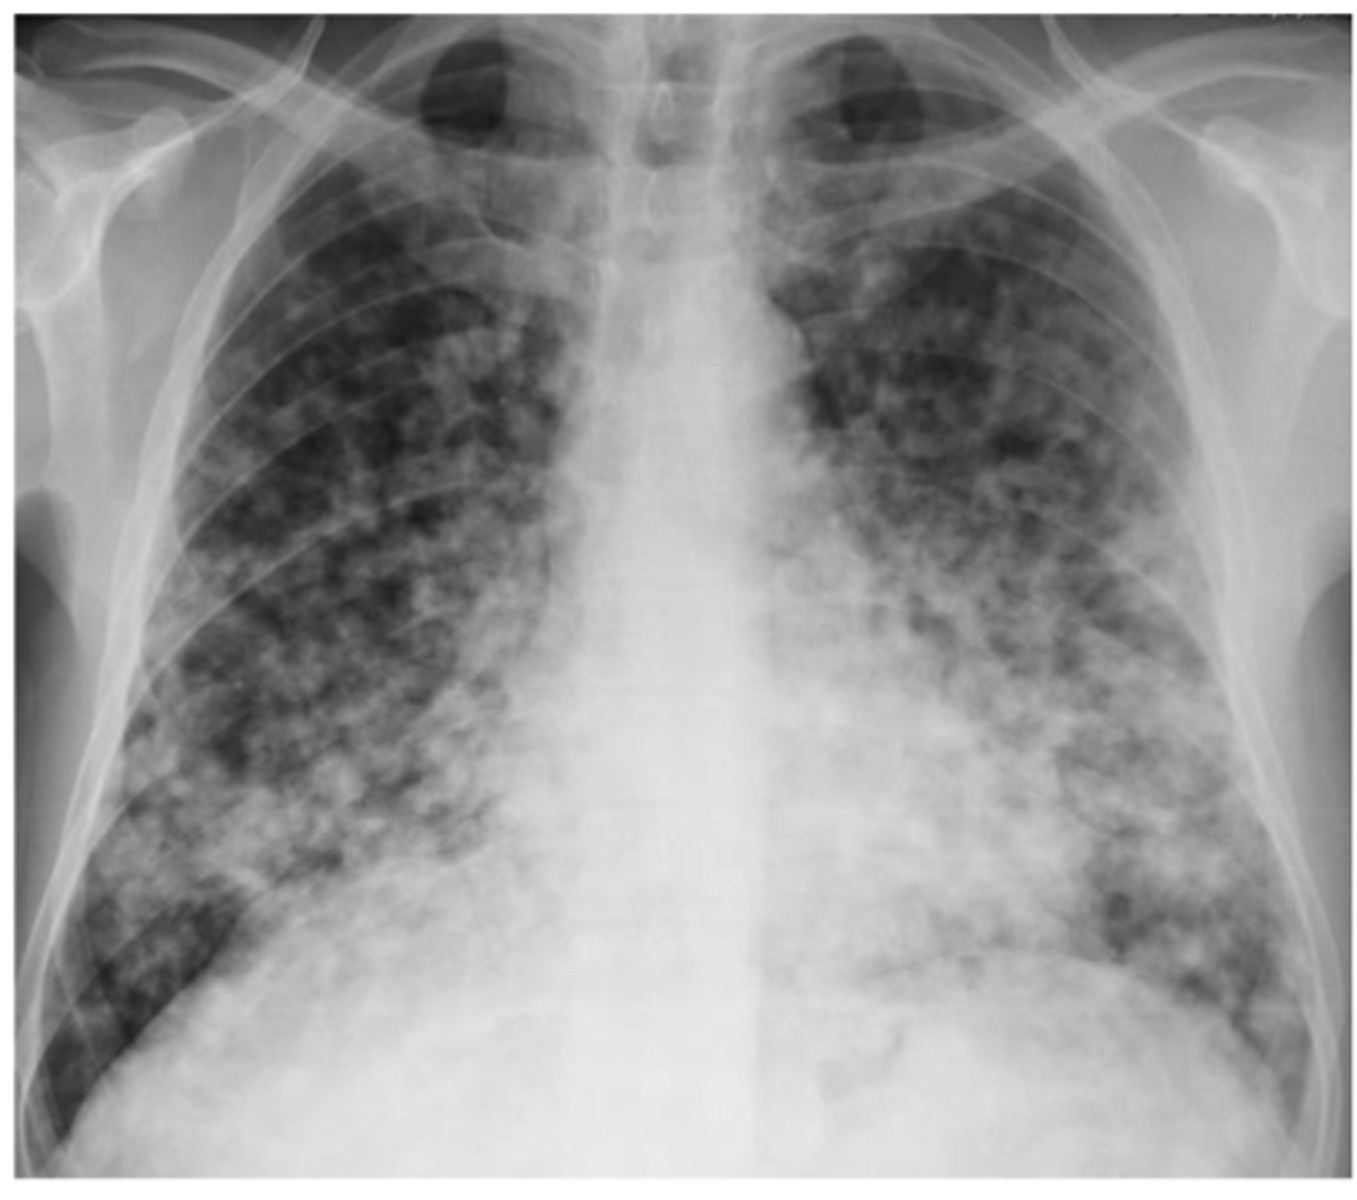

What is the pattern on the image of the back of the card?

Cystic PJP - PA chest radiograph shows diffuse bilateral reticulonodular interstitial infiltrates

<p>Cystic PJP - PA chest radiograph shows diffuse bilateral reticulonodular interstitial infiltrates</p>